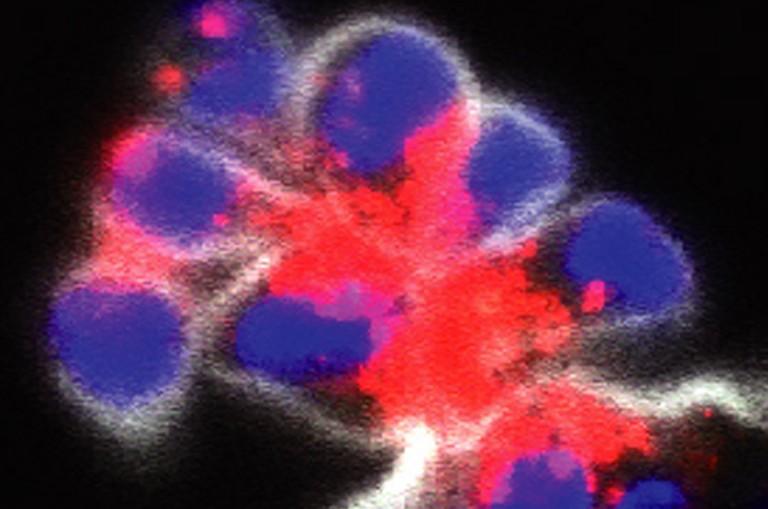

Miao Lab's Kengo Nozaki et al. publish article in Nature, 'Caspase-7 activates ASM to repair gasdermin and perforin pores'

ABSTRACT: Among the caspases that cause regulated cell death, a unique function for caspase-7 has remained elusive.